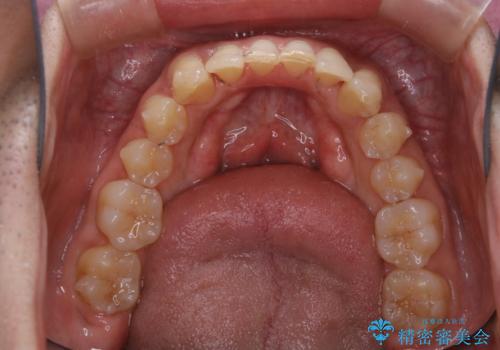

マウスピース矯正の途中にPMTCで白い歯に

- インビザラインによるマウスピース矯正中に歯の黄ばみ・ステインが気になるとのことでした。PMTC60分コースを行いました。

マウスピース矯正インビザライン治療では、歯の表面にアタッチメントという突起を設定します。(アタッチメントは歯の動きを効率的に移動するためのものです)

アタッチメントが歯に付くと、表面が凸凹し磨き残しが多くなったりと、プラークや歯石・着色がつきやすくなることがあります。

矯正治療中もPMTCを定期的に行い、専門的な機械でしっかりと汚れを除去することがおススメです。